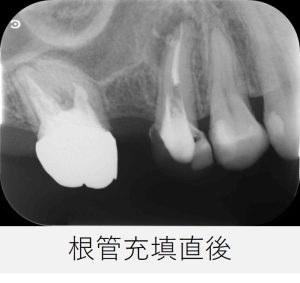

- 根管充填後の状態を確認するため、レントゲン写真を撮影しました。

- 根の先だけでなく、側方に広がっていた黒い影の原因と考えられていた側枝にも、根管充填材がしっかりと行き届いていることが確認できました。

▲根管充填直後のレントゲン画像

根の先、側枝部分まで、しっかりと材料が充填されています。